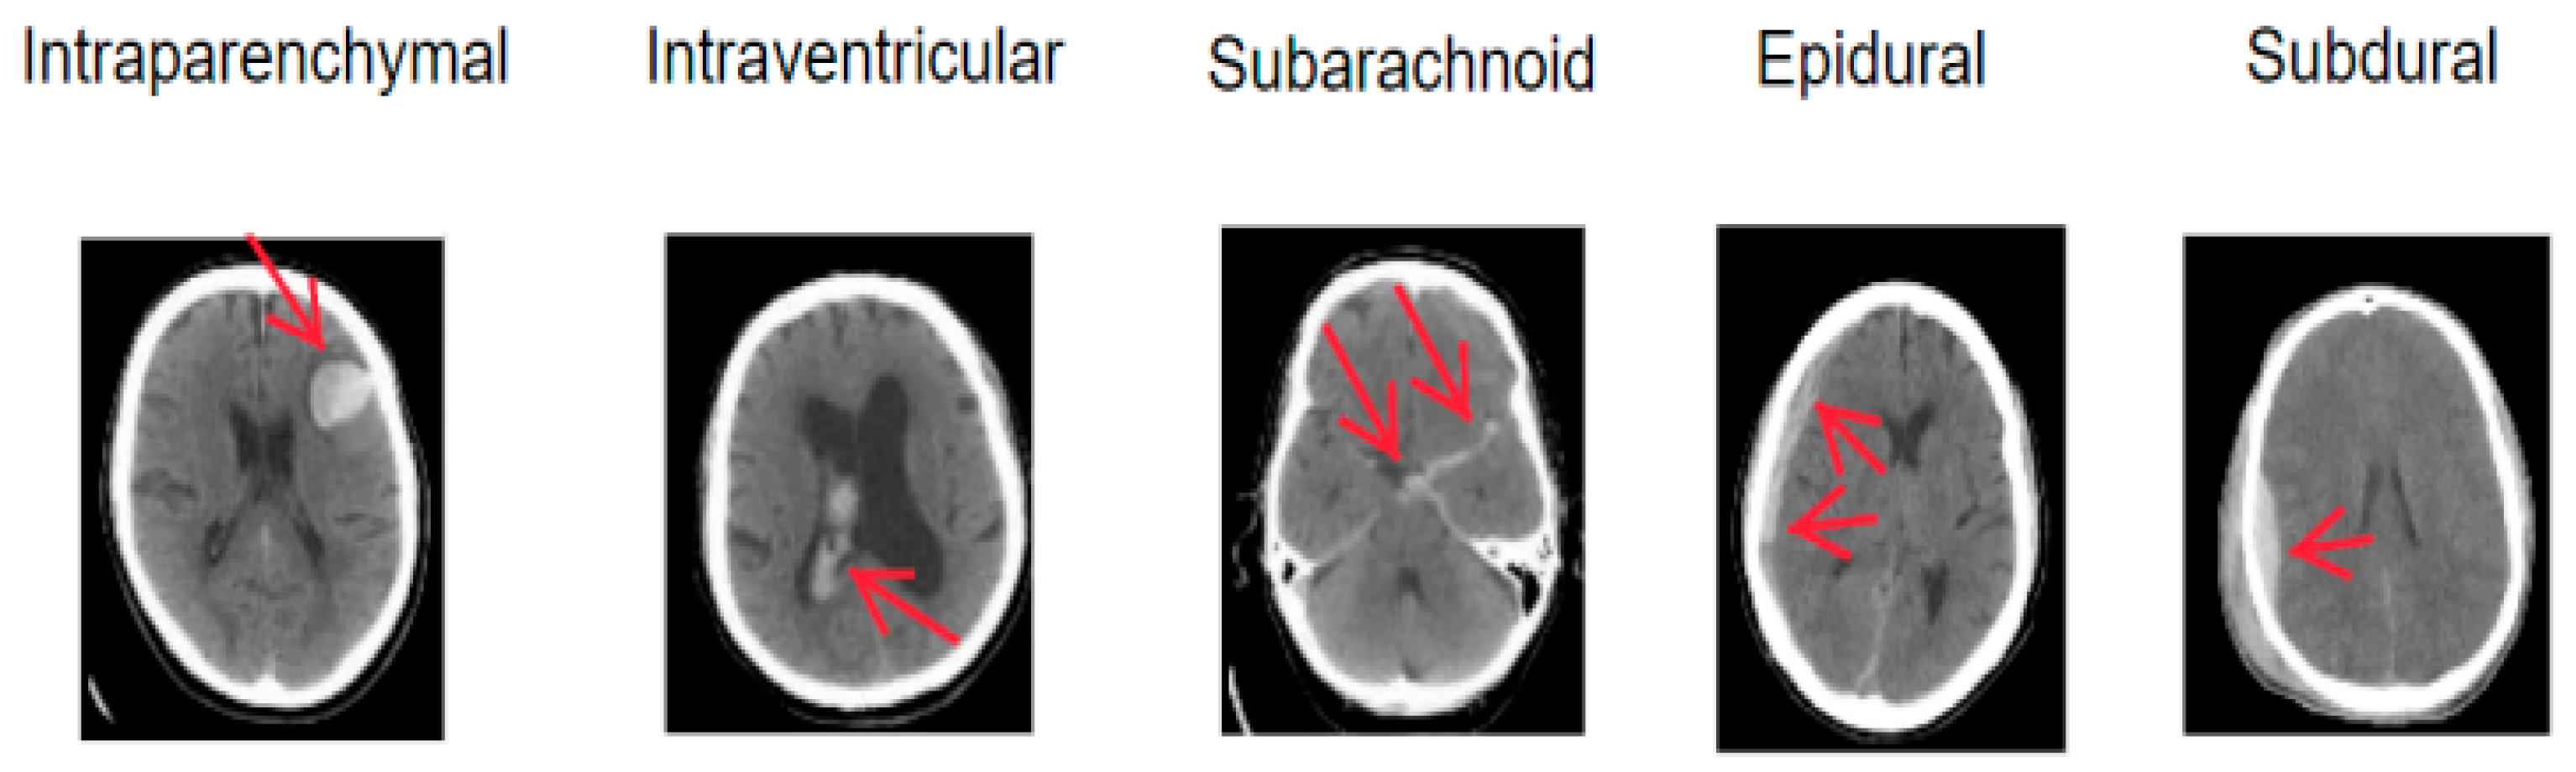

1. Introduction

4.1. Dataset